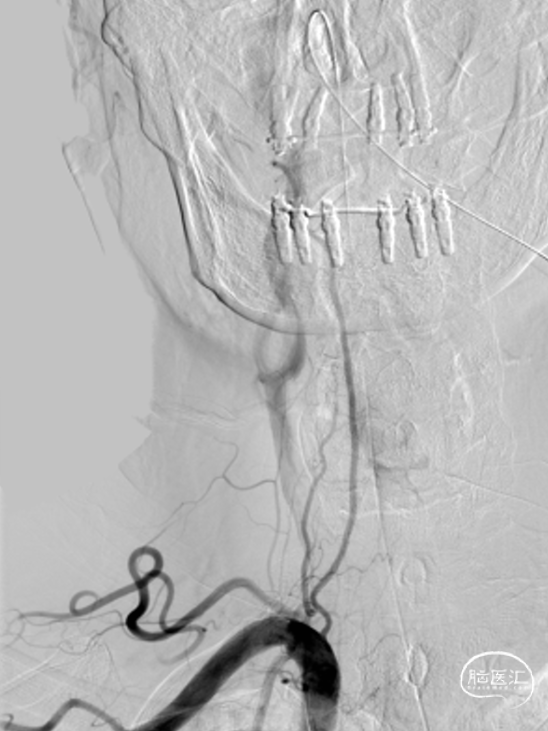

外院造影

➢L-V4闭塞

➢R-V4闭塞

➢R-ICA:后交通开发代偿基底动脉

右侧颈内动脉、左侧椎动脉联合造影,确认闭塞段。